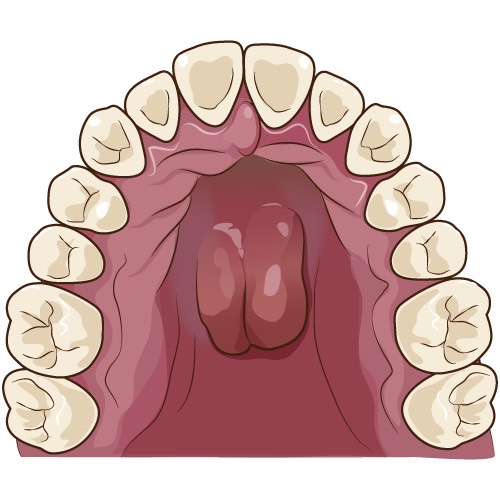

下顎隆起

口蓋隆起

歯槽隆起